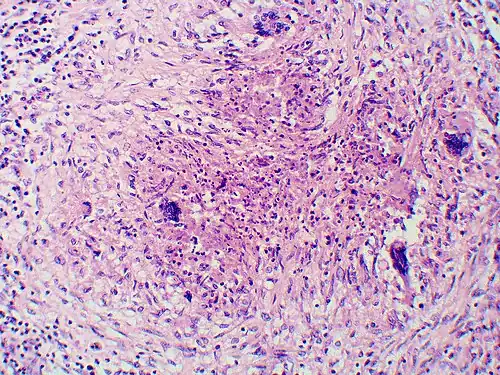

Large, broadly-based budding yeast cells characteristic of Blastomyces dermatitidis in a GMS-stained biopsy section from a human leg.

Inhaled conidia of Blastomyces are phagocytosed by neutrophils and macrophages in alveoli. Some of these escape phagocytosis and transform into the yeast phase rapidly. Having thick walls, these are resistant to phagocytosis. Once they have transitioned to the yeast phase, the Blastomyces cells express the protein BAD-1, which helps the yeast cells attach to host cells, and also impairs the activation of immune cells while inhibiting the release of tumor necrosis factor. [23] In lung tissue, the cells multiply and may also disseminate through blood and lymphatics to other organs, including the skin, bone, genitourinary tract, and brain. The incubation period for pulmonary blastomycosis is 3 to 15 weeks, although 30–50% of infections are asymptomatic.[24]

Once suspected, the diagnosis of blastomycosis can usually be confirmed by demonstration of the characteristic broad-based budding organisms in sputum or tissues by KOH prep, cytology, or histology.[27] Tissue biopsy of the skin or other organs may be required to diagnose extra-pulmonary disease. Blastomycosis is histologically associated with granulomatous nodules.